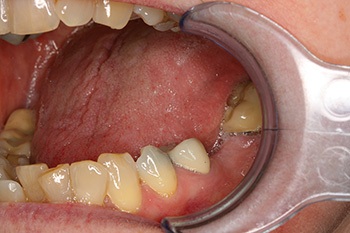

Fig. 3: Pre-op PA

Frances was seen by my colleague, a prosthodontist, who treatment-planned her to have the premolar removed and a single implant placed into the molar site. That implant would then be used to support a cantilever bridge, replacing both the molar and premolar teeth.

Now, this wasn’t something I had planned myself, but I was comfortable using short implants and cantilever restorations—I just hadn’t put the two together before!

So, I placed an 8 mm-long Ankylos implant into her lower left first molar site. Three months later, the prosthodontist restored it with a cantilever bridge.